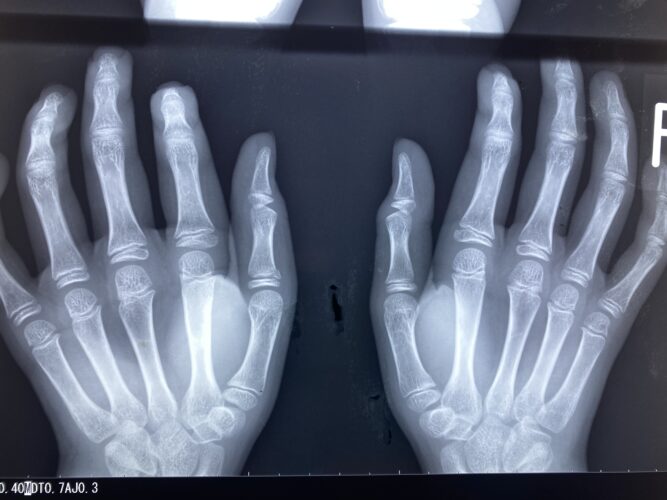

さわやか千葉県民プラザ(指骨骨折)